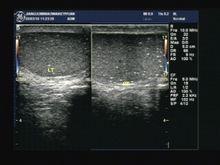

1、超聲檢查

(1)每個切面均能發現5個以上1~2mm大小的點狀強回聲,後方無聲影。

(2)瀰漫分布於睪丸實質內。睪丸微石症聲像圖具有特徵性表現,超聲即可診 斷,因此不必進行侵害性的檢查。